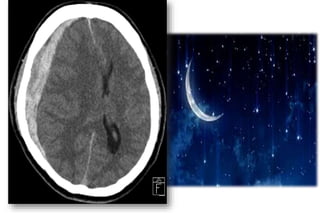

CT-SCAN

Acute SDH

The clot is bright or mixed-density

Crescent-shaped (lunate), may have a less distinct

border, and does not cross the midline due to the

presence of the falx